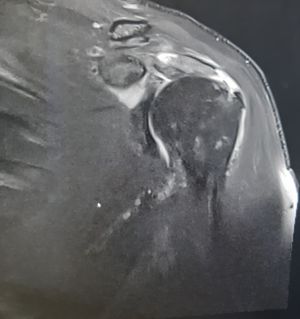

Bei der Verrenkung wird meist das Labrum (Gelenkslippe) von der knöchernen Pfanne gerissen, manchmal auch mit knöchernem Fragment (Bankartläsion). An der Rückseite des Oberarmkopfes entsteht eine Eindellung (Hill-Sachs-Delle), die aber in den seltensten Fällen therapiebedürftig ist.

Die Diagnosestellung erfolgt in der Akutphase klinisch und mit einer Röntgenaufnahme in zwei Ebenen. Um Begleitverletzungen besser erkennen zu können, ist im Intervall eine Arthro-MRT (spezielle MRT mit Kontrastmittel) notwendig. Bei chronischen Luxationen sollte außerdem eine Computertomographie durchgeführt werden, um knöcherne Defekte besser zu beurteilen.